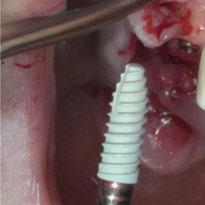

Para ilustrar el proceso, presentamos el caso de una mujer joven diagnosticada de carcinoma adenoide quístico en la región posterior del hemipaladar izquierdo (Figuras 1 y 2). El procedimiento quirúrgico realizado fue una

maxilectomía parcial que incluyó las piezas 24-26 y desde el reborde alveolar hasta la base del cráneo (Figuras 3 y 4). En este caso, la órbita y el globo ocular pudieron ser preservados. La reconstrucción inmediata se realizó mediante un colgajo de músculo temporal homolateral (Figura 5) y el defecto de la fosa temporal fue cubierto mediante una malla de titanio. Posteriormente, la paciente recibió radioterapia (Figuras 6 y 7). 2 años más tarde se diseñó un IS con anclaje en el arbotante nasomaxilar, zona subnasal izquierda

y lo que se pudo preservar del hueso malar. Se añadió una malla sinterizada infraorbitaria para dar volumen a la mejilla y se planificaron dos brazos de conexión que emergieran en las posiciones 24 y 26 de forma subgingival (Figuras 8 y 9). La superficie interna que apoyaba en el hueso era de titanio microrrugoso, y la superficie externa y conectores de titanio pulido y hexágono externo universal (Figuras 10 y 11). La cirugía se hizo bajo anestesia general en infiltración con anestesia local (4% articaína, 1:100.00 epinefrina), levantando el

colgajo cutáneo de la mejilla por vía intraoral, preservando el colgajo temporal para no comunicar con el remanente de la cavidad naso maxilar (Figura 12). Se emplearon 10 tornillos de osteosíntesis de 1,9 mm y la estabilidad primaria obtenida fue excelente (Figura 13)